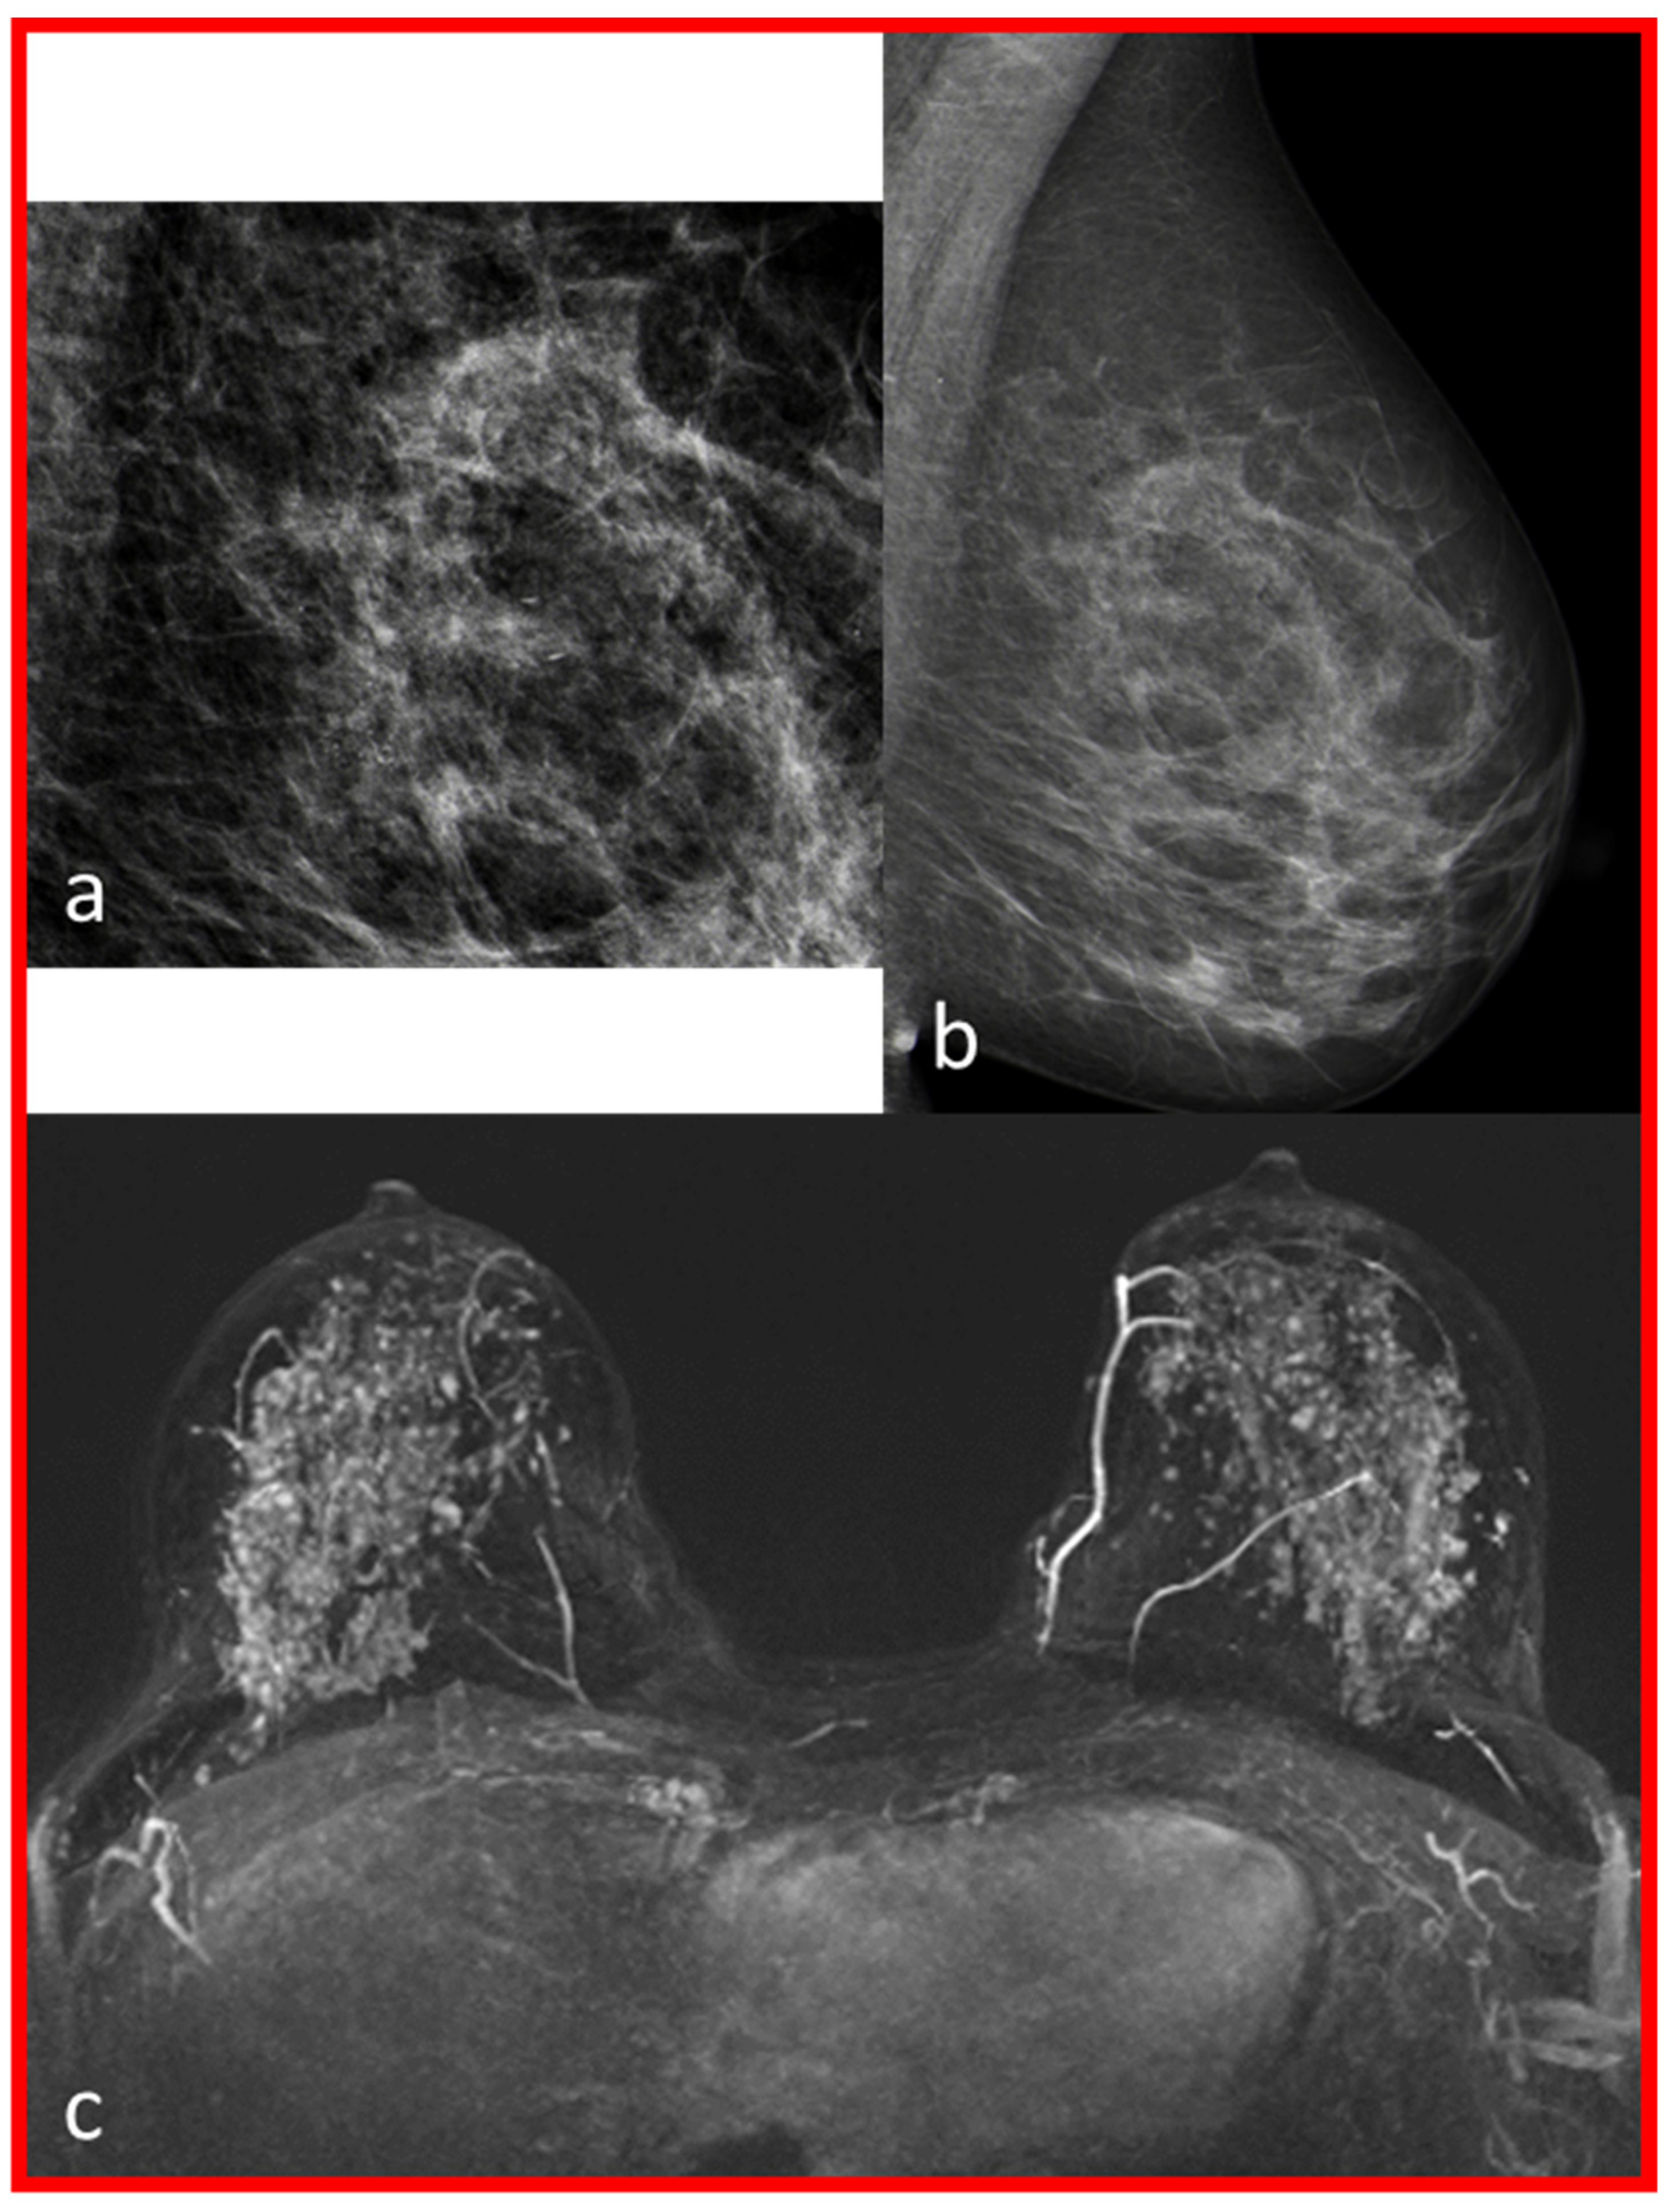

| 1 | 2 | Moderate | B | Intermediate-grade DCIS (6.5 cm) | No contrast enhancement in the position of macrocalcifications, multiple small foci on both sides. |

| 2 | 1 | Marked | C | Low-grade DCIS (0.15 cm) | No contrast enhancement in the position of macrocalcifications. |

| 3 | 1 | Marked | C | Low-grade DCIS (5.6 cm) | No contrast enhancement in the position of macrocalcifications, multiple cysts on both sides. |